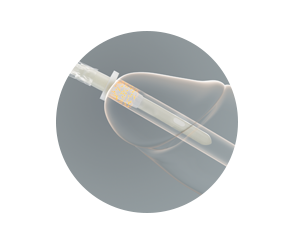

Beschermende sleeve

- zorgt ervoor dat de katheter overal kan worden vastgepakt

- vormt een barrière tegen ziektekiemen

Bewezen bescherming tegen pathogenen – beschermende sleeve

De VaPro™ katheter met sleeve slaagt voor de ASTM F1671-test en geeft dus de garantie dat deze beschermt tegen pathogenen die urineweginfecties kunnen veroorzaken.

De American Society for Testing and Materials (ASTM) is een internationale organisatie die technische standaards voor een breed scala aan materialen ontwikkelt en publiceert op basis van vrijwillige consensus. ASTM heeft tot nu toe ongeveer 6000 testmethoden uitgevoerd en gepubliceerd.

ASTM F1671 is een voldoet / voldoet-niet test die is opgezet om aan te tonen of beschermend materiaal de overdracht van via bloed overdraagbare pathogenen voorkomt.

De VaPro™ katheter met sleeve werd getest. In de test werd één zijde van het sleevemateriaal blootgesteld aan een oplossing met een type virus dat bacteriofaag wordt genoemd. De resultaten tonen aan dat de virussen het materiaal van de sleeve niet kunnen doordringen.

Klik hier voor een samenvatting van het klinisch en laboratoriumbewijsmateriaal dat aantoont dat intermitterende katheters met een sleeve het risico op externe contaminatie tijdens voorbereiding en inbrengen van de katheter helpt verminderen. Deze reductie kan mogelijk het risico verminderen dat bacteriën de blaas binnendringen.